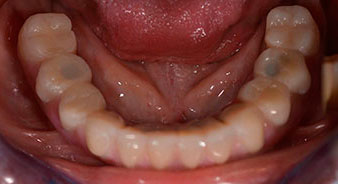

Die 64-jährige Patientin wurde mit einer Unterkiefer-Restbezahnung 38, 33 und 43 und einer klammerbefestigten Interimsprothese im Unterkiefer vorstellig (Abb. 1 und 2).

Zur Planung und Risikominimierung wurde eine dreidimensionale Volumentomografie (DVT, Planmeca) erstellt. Dieses zeigte, dass die Qualität und Quantität des Knochens für eine Operation und Sofortversorgung nach der Fast & Fixed-Methode ausreichend war. Nach Protokoll dieses Konzeptes wird in Regio 35, 32, 42 und 45 implantiert. Durch die bis zu 45-Grad-Schiefstellung der distalen Implantate wird das Durchtrittsprofil nach posterior verlegt und ein größeres Stützpolygon erreicht (Abb. 3).